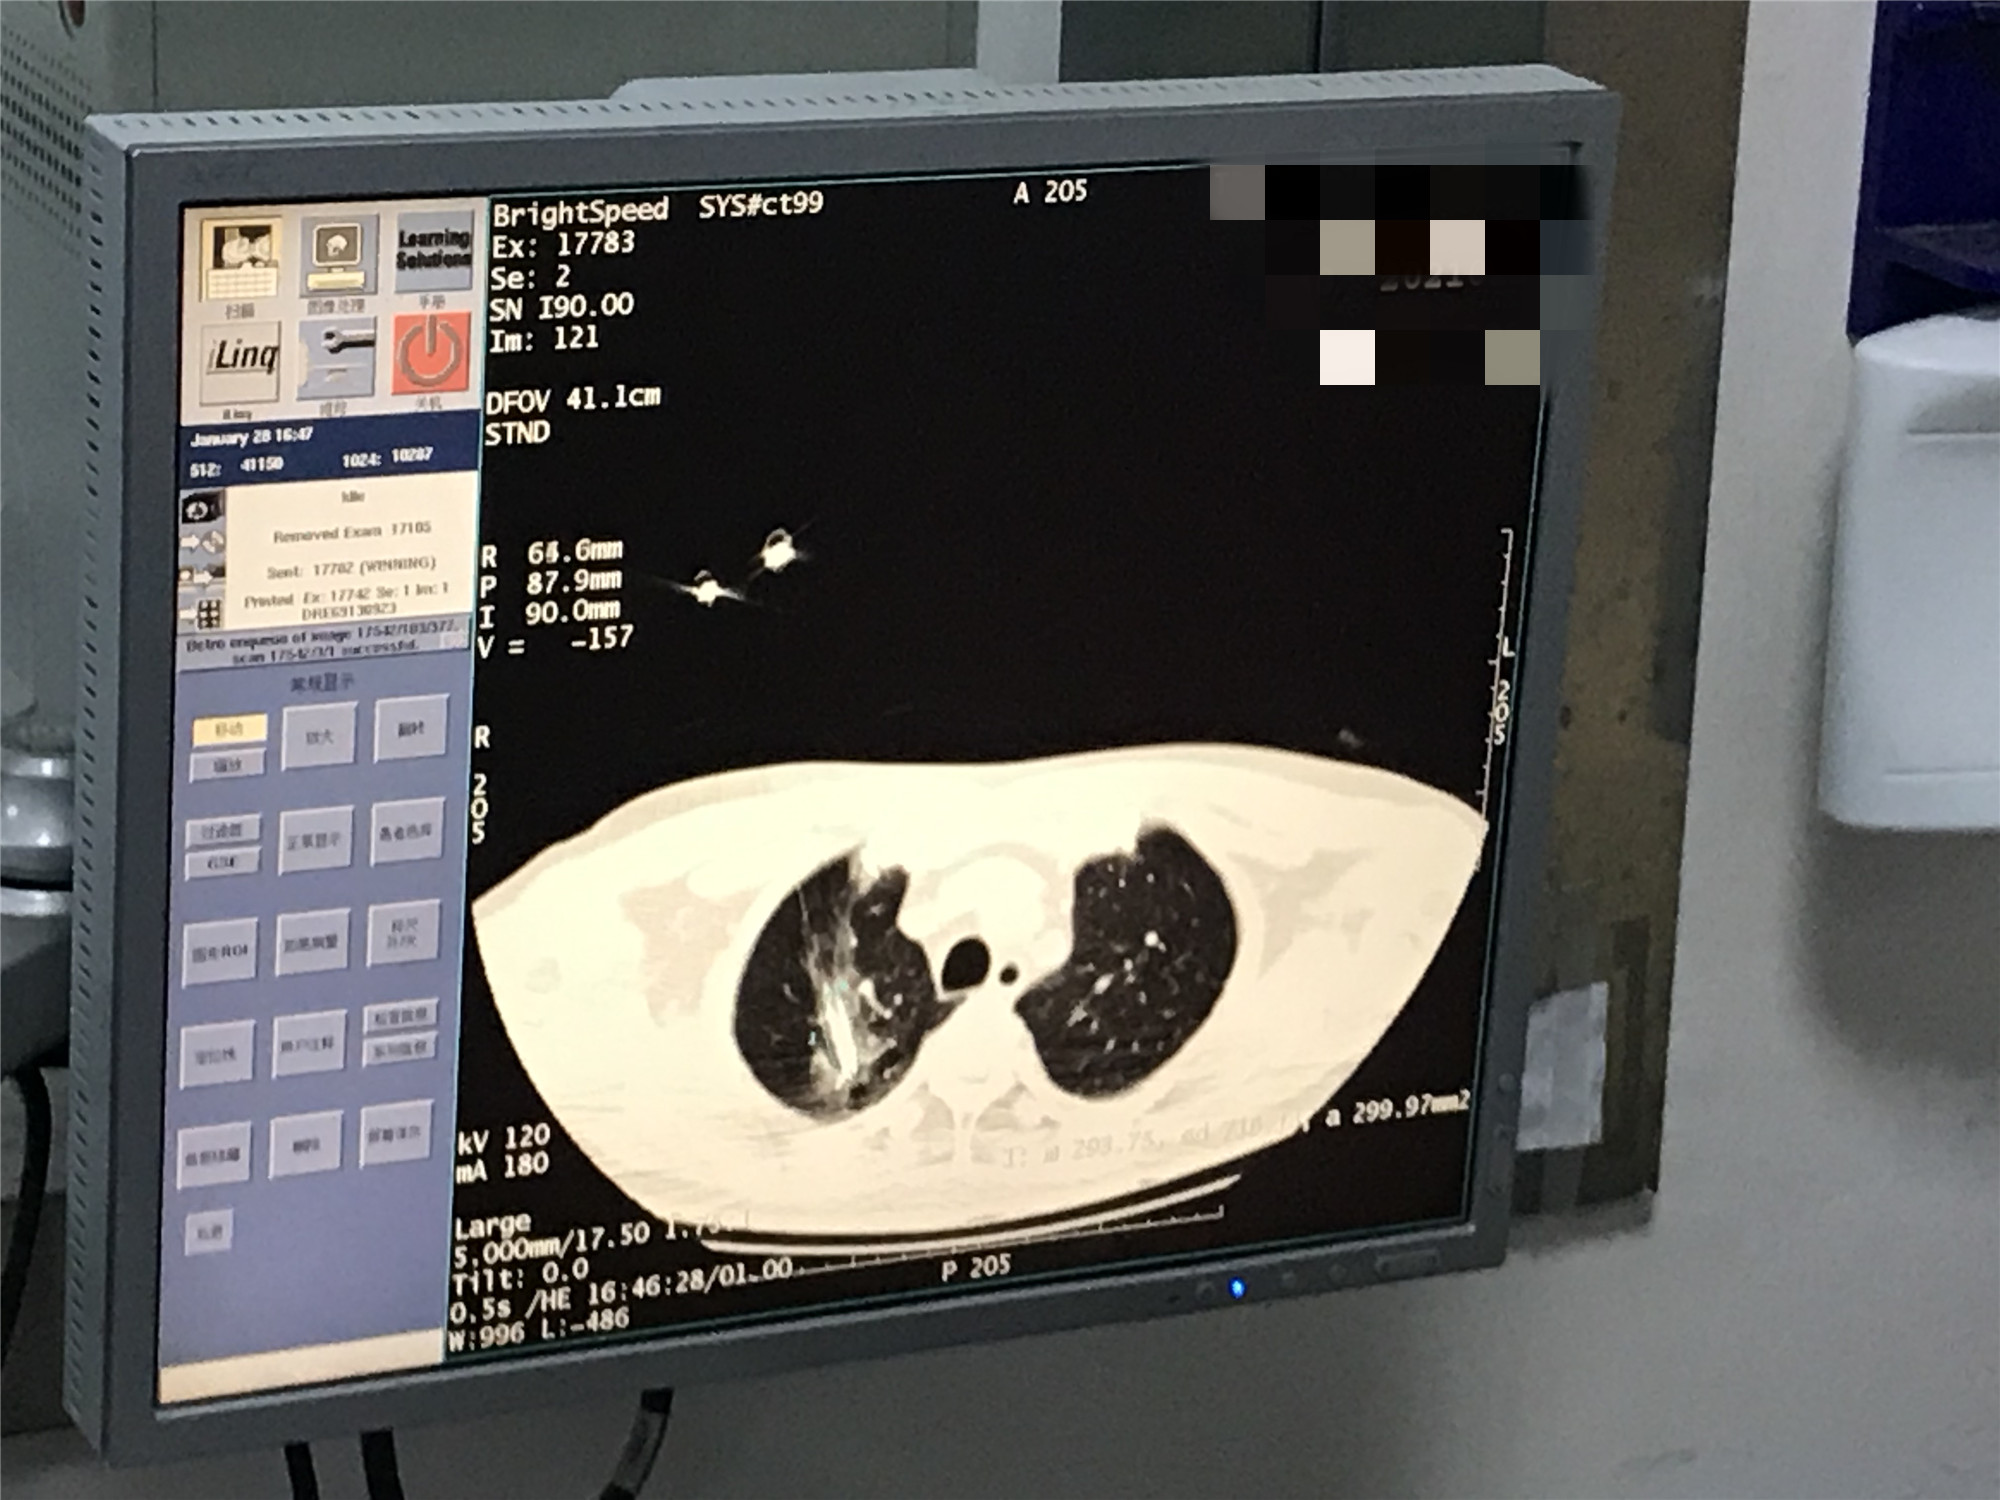

2021年1月份肺部氩氦刀手术